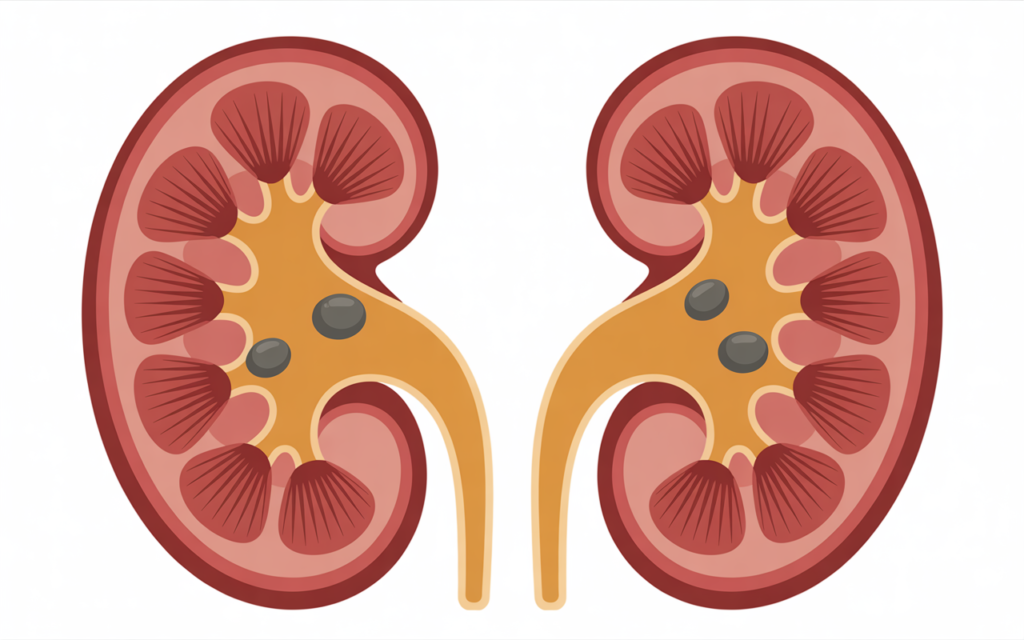

What Are Kidney Stones and Why They Form

Kidney stones are solid mineral and salt deposits that develop inside the kidneys. These stones form when urine becomes concentrated, causing minerals like calcium, oxalate, and uric acid to crystallize.

Several factors contribute to stone formation:

- Dehydration and inadequate water intake.

- High intake of salt and red meat in kidney stone formation.

- Low citrate levels in urine, which normally prevent crystals.

- Genetic predisposition and certain medical conditions.

Without prevention, stones often return. Research shows a recurrence of kidney stones in nearly 50% of patients within five years.